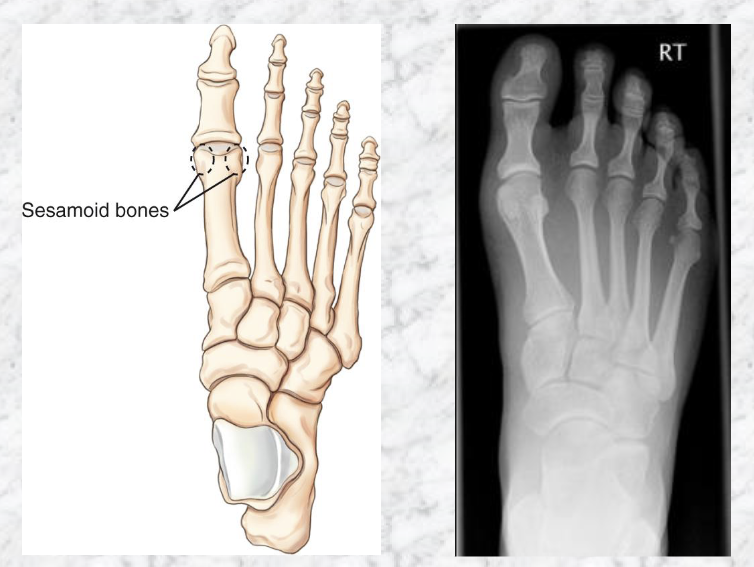

Sesamoid bones

Where are they?

Embedded in tendons

Present near joints

Plantar surface of foot